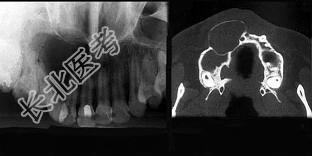

- 多项选择题面裂囊肿(影像表现如组图)包括 ( )

A、球上颌囊肿

B、鼻腭囊肿

C、正中囊肿

D、鼻唇囊肿